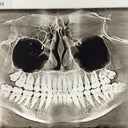

So far: yesterday I had spacers put in to make room for molar bands in the back. From where the spacers are placed, it seems he wants to do bands on all 8 molars, plus all 4 2nd bicuspids. I realized after I got home that you can see my upper 2nd bicuspids when I smile, so at my next appointment I am going to ask if he would be willing to try with regular brackets on those 2 teeth. I know everyone says "just be proud you're doing something for yourself!" but how I look for 2 years of my life does matter. The spacers are still not really causing me pain, except when I chew, but I can chew normal foods gently. I think maybe I keep comparing this to the wisdom teeth removal pain, and I have a feeling nothing will ever come close to the pain of a dry socket. I'm going to attach some pictures of my teeth before the spacers... Don't judge the terrible picture taking :)